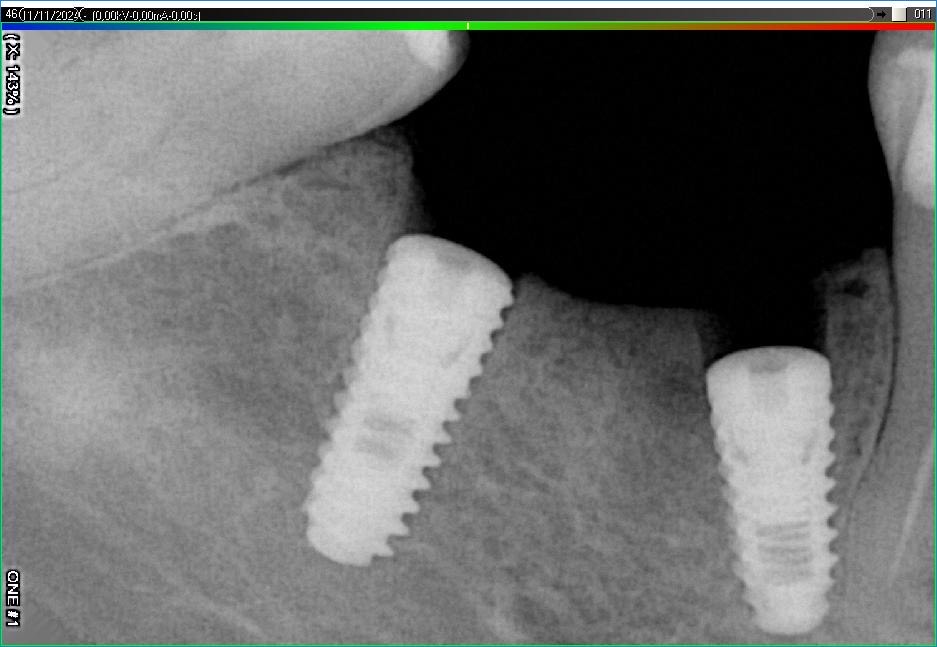

Імплантація